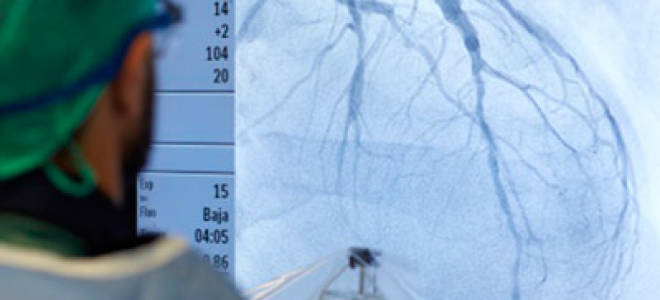

Инфаркт как проводится операция Инфаркт миокарда: особенности оперативного лечения Операция при инфаркте миокарда необходима в большинстве случаев. Она помогает восстановить...